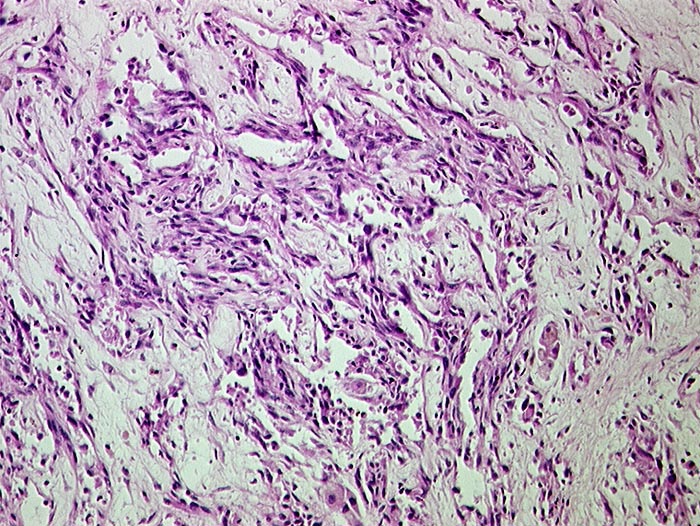

PathoPic ID 686 - Angiosarkom

Angiosarkom

maligner Tumor

Leber

Leber, Gallenwege, Pankreas

Gefässräume ausgekleidet durch atypisches Endothel.

Histologie